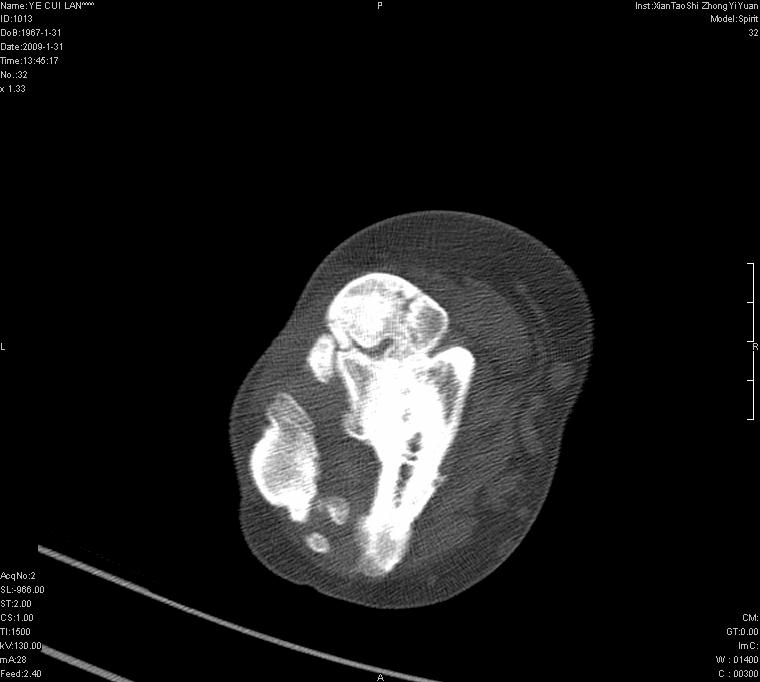

以下是引用王明发在2009-2-9 11:53:00的发言:[br]支持夏科氏关节,必要时行脊髓mri检查 [br]夏科氏关节是指由于某些神经系统疾病引起的关节病变,也被称为神经性关节炎。常见病因有脊髓痨、脊髓空洞症等。原发的神经病变可以造成关节深部感觉障碍,对于关节的震荡、磨损、挤压、劳倦不能察觉因而也不能自主地保护和避免,而神经营养障碍又可使修复能力低下,使病人在无感觉状态下造成了关节软骨的磨损和破坏,关节囊和韧带松弛无力,易形成关节脱位和连枷关节。关节面的破坏和骨赘的脱落变成关节内游离体。关节外形饱满肿胀,内有出血和渗出。这种病早期并无疼痛,不易被病人重视,仅表现为关节肿胀、无力、活动过度、动摇不稳。关节肿胀、无痛、活动范围超常是本病的重要特征。x光片可见有关节骨端广泛破坏、硬化或呈奇异形态,骨赘形成,关节间隙不规则或增宽,周围软组织钙化、关节内游离体、骨碎片等。结合x光片及临床症状,病人又有神经系统原发病症,即可确诊

以下是引用hhcckk在2009-2-9 14:31:00的发言:[br]夏科关节的六大表现[br]1.关节软组织肿胀。[br]2.关节的脱位与半脱位。[br]3.关节内的游离体。[br]4.关节面硬化,新骨形成。[br]5.骨质萎缩与破坏。[br]6.关节结构的紊乱。[br]加上患者无明显疼痛,诊断的把握性比较大